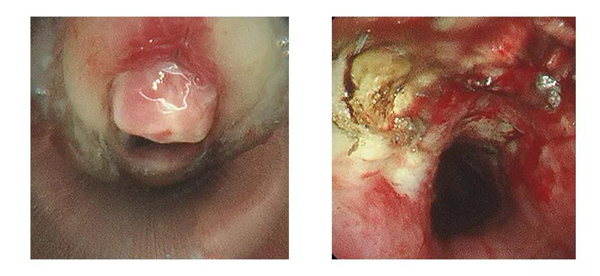

入院后,王洪武主任结合患者身体情况,制定周密的手术方案,在气管镜室内,行支气管镜治疗。全麻下经口进硬镜,气管切开口上端可见一肉芽肿,“横”在气道中间,使管腔狭窄约80%。王洪武主任遂即给予圈套器套取、并采用低温等离子将肉芽大部分清除,管腔较前明显增宽,狭窄约10%。一个小时后,杨阿姨狭窄处气道明显扩大,通气得到显著改善,手术顺利完成。

治疗前:管腔狭窄约80% 治疗后:狭窄约10%